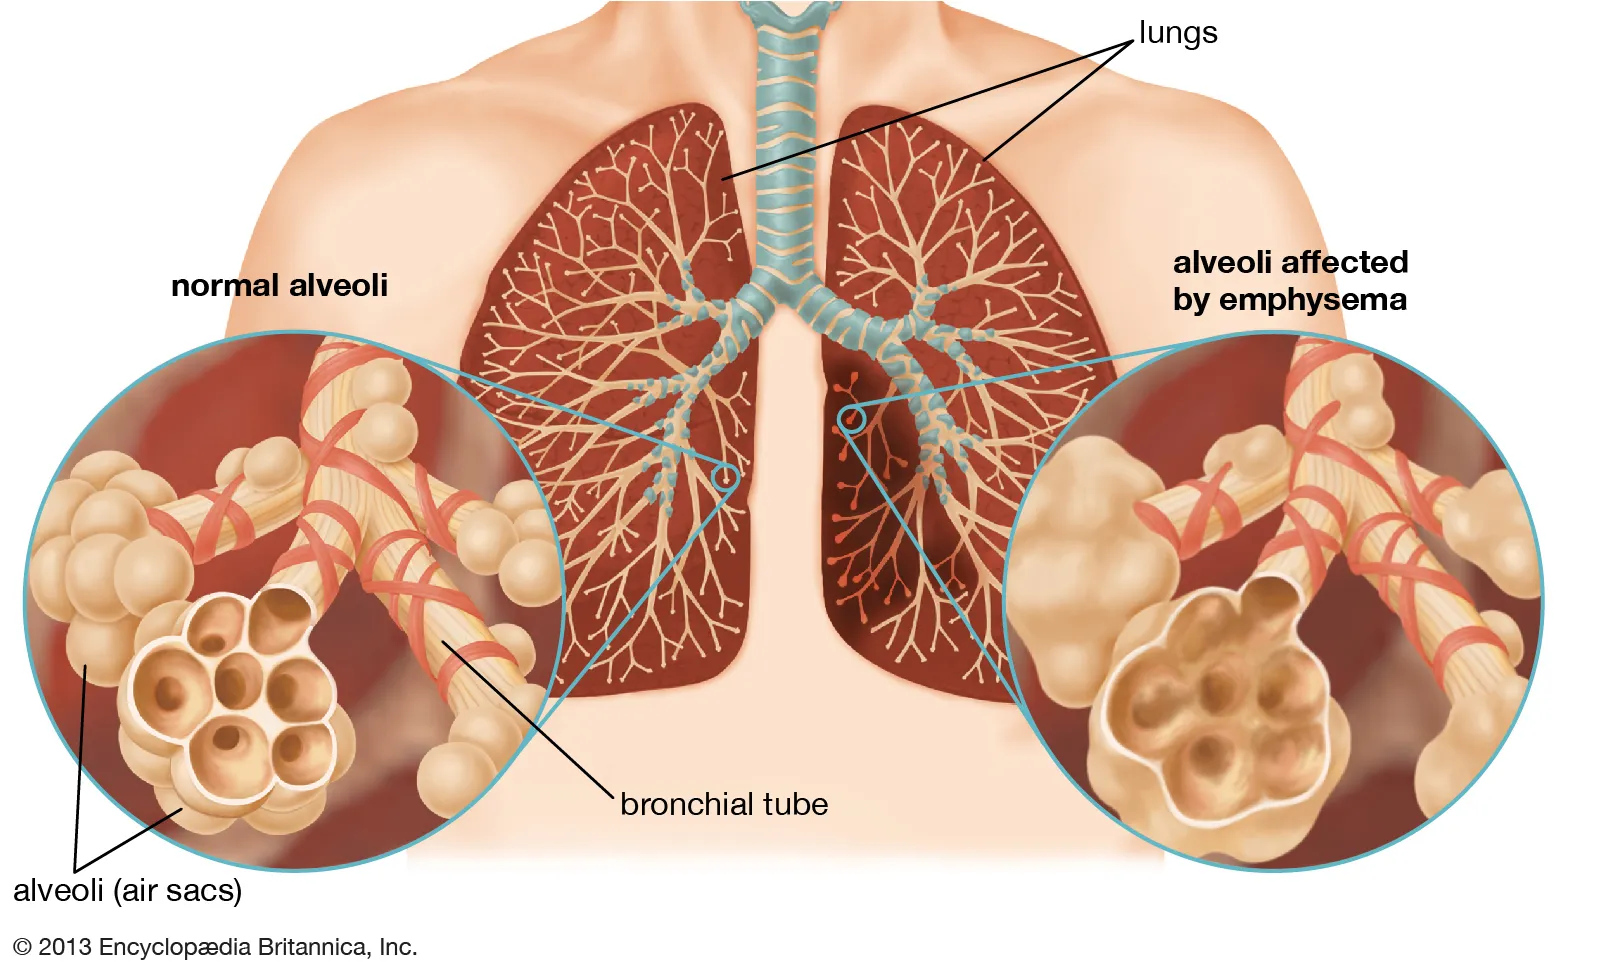

COPD

A Condition involving constriction of the airways and difficulty or Discomfort in Breathing.